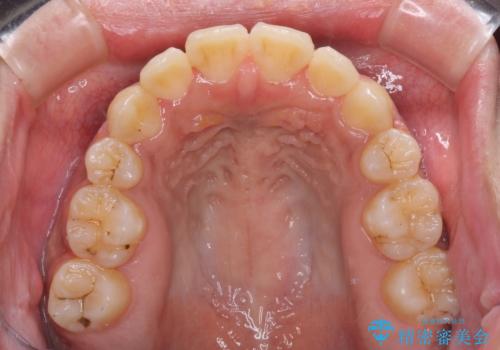

- 八重歯と上下前歯のでこぼこを気にして来院された患者様です。

上下前歯部叢生のスペース獲得のため、上下顎左右小臼歯各1歯(計4本)と全ての親知らずを抜歯して、矯正治療を行うこととしました。

上下の正中位置が大きくずれていたため、治療期間の長期化や正中が合わないまま終了することが予想されましたが、思っていた以上にスムーズに歯が移動し、満足いただける仕上がりとなりました。